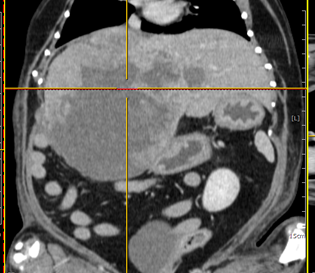

간종양